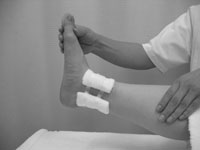

初診(12月18日)整復時の写真。脛骨下端の後方にある骨片を、前方に押し上げる。 |

患部の固定、腫脹軽減を目的に脛骨内果部の後方、側方より圧迫枕子を加えた。腓骨は転位がないため前後方向からの圧迫枕子のみとした。両骨とも患部の動揺を防ぐため、テープによる固定を行った。冷湿布を行い、大腿中央より足先にかけて背側にクラーメルシーネをあて、包帯にて固定を行った。固定肢位は膝関節軽度屈曲位、足関節良肢位とした(図3)。右患側肢への体重付加を禁止。松葉杖歩行を指示した。

整復後の転位を防ぐため、内果部に綿花枕子をあてる。 |

整復後の転位を防ぐため、外果部に綿花枕子をあてる。 |

テーピによる固定 |

クラーメル、包帯による固定 |